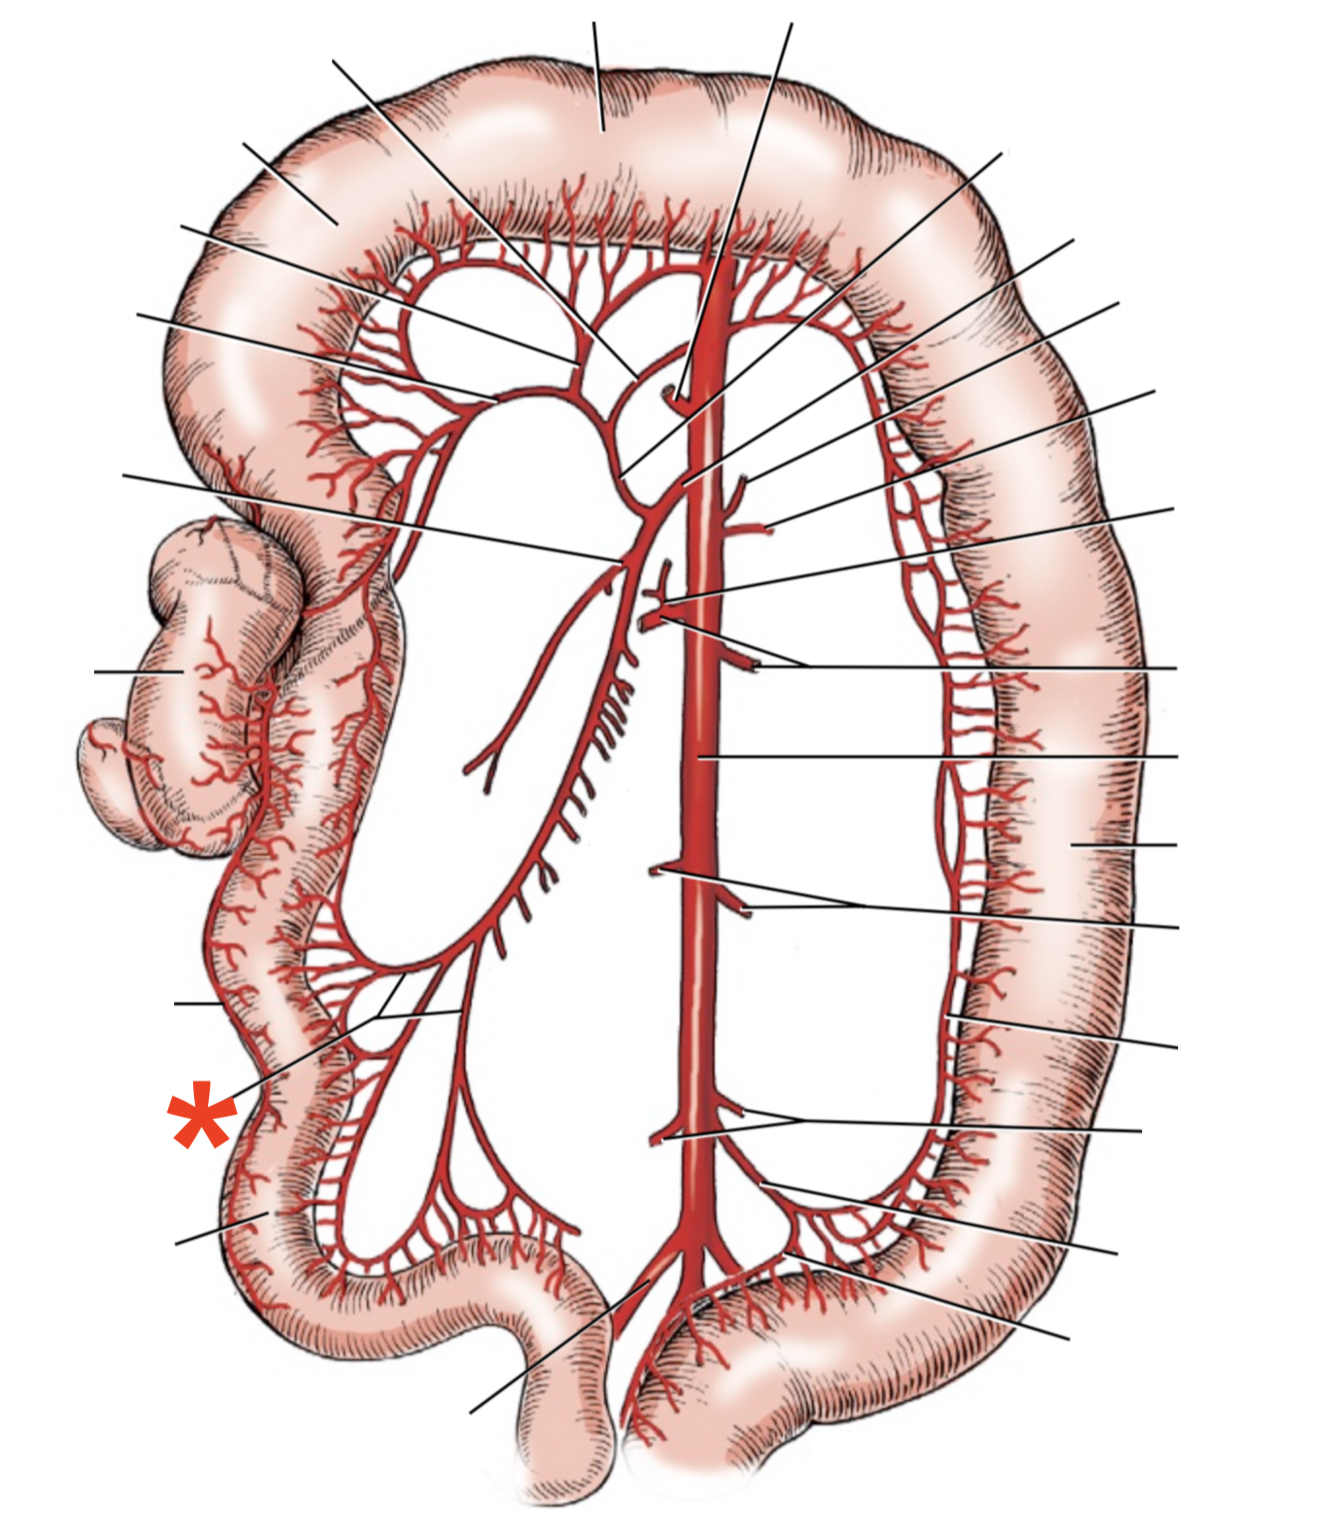

A

A. mesenterica cranialis

15

Q

A

A. pancreaticoduodenalis caudalis

16

Q

A

Aa. jejunales

17

Q

A

A. ilei

- Anastomises with r. ileus mesenterialis a. iliocolica

18

Q

A

A. ileocolica

19

Q

A

A. colica dextra

20

Q

A

A. colica media

21

List the branching of *a.* *mesenterica* *caudalis*

* *A. colica sinistra*

* *A. rectalis cranialis*

List the branches of *a.* *mesenterica* *cranialis*

* *A.* *pancreaticoduodenalis* *caudalis*

* *Aa. jejunalis*

* *A. ilei*

* Common trunk

* A. colica media

* A. colica dextra

* *A. ileocolica*

* *R. ilei mesenterialis*

* *A. cecalis*

* *R. colicus*